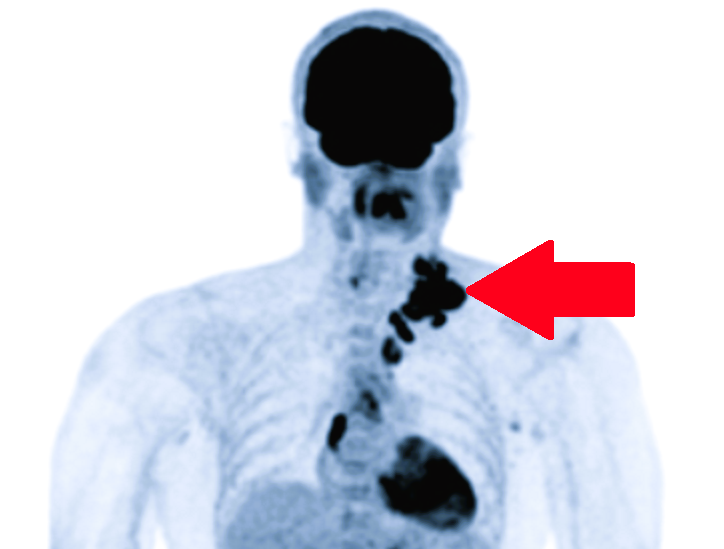

ТЭТ-КТ: поражение левых надключичных и внутригрудных лимфоузлов

☑️КТ, МРТ, ПЭТ-КТ: эти методы позволяют увидеть глубоко расположенные лимфоузлы (в брюшной полости, в грудной клетке), которые нельзя прощупать руками. ПЭТ-КТ особенно эффективен для поиска метастазов, так как «подсвечивает» даже небольшие скопления активных раковых клеток.

Множество научных статей демонстрируют превосходство ПЭТ-КТ в определении стадии заболевания для многих видов рака.